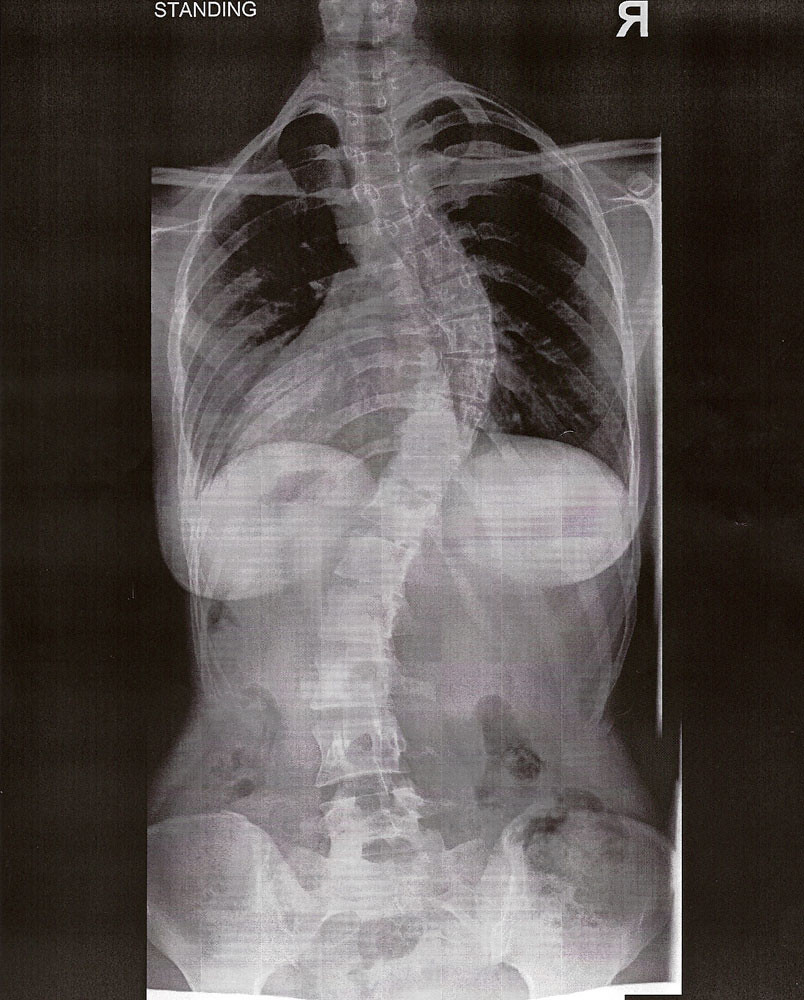

Standing xrays. Standing xrays show scoliosis of 63° at T27 and 54 Can Chest X Ray Show Scoliosis Scolioses) is defined as an abnormal lateral curvature of the spine. Thoracic scoliosis usually has a rotational element and so assessment of heart size may not be accurate; To estimate the usefulness of chest radiographs for scoliosis screening, the sensitivity and specificity of chest radiographs were. A sideways curve in the part of your spine that makes up your upper. Can Chest X Ray Show Scoliosis.